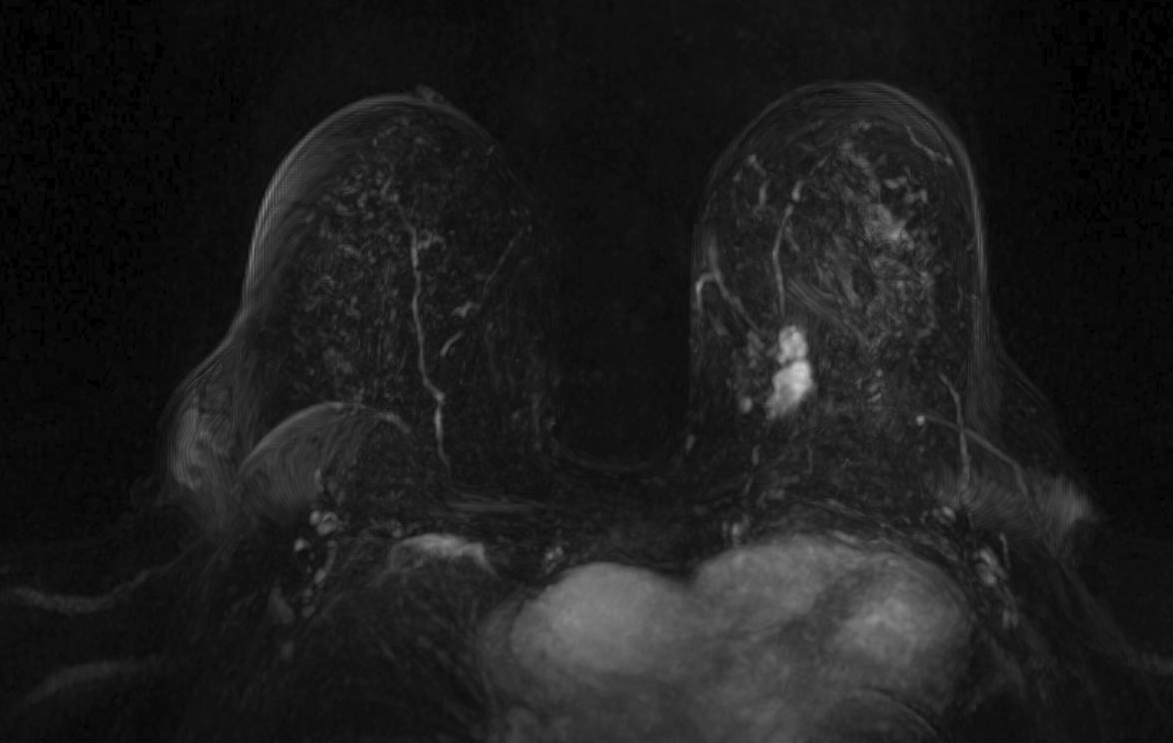

Magnetic resonance imaging (MRI) has been used as an adjunctive screening tool, mainly for women who may be at increased risk for the development of breast cancer. Example images of MRI are shown in fig. 5 with T1 contrast enhancement. MRI for screening has not been very popular in women with average risk due to concerns about the low specificity leading to additional biopsies, time and cost of technology [26]. Breast MRI sensitivity values reported in high risk screening studies range from 93% to 99%. Despite its high sensitivity, breast MRI has been reported to have variable specificity, ranging from 50% to 85% [27]. These number of sensitivity and specificity depends on the type of tumor, size of tumor, age of patient, and where it is localised.